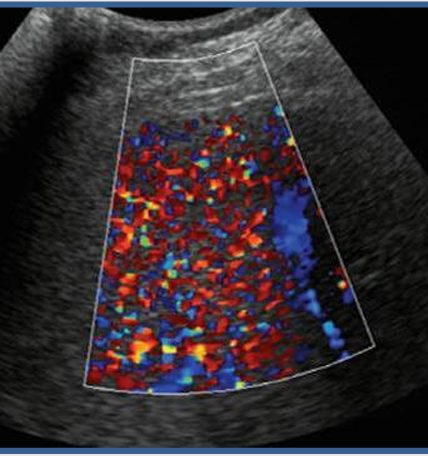

what is happening in this image?

rupture of microbubbles